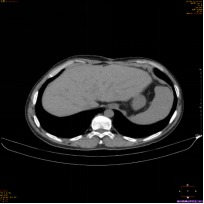

(图4)

上图为一名53岁男性,乙肝、肝硬化随访复查,AFP及超声检查均为阴性;图1为腹部CT平扫显示,肝左叶体积增大,肝实质内未见明确异常密度结节及肿块;图2、图3分别为磁共振平扫T2WI、弥散成像显示,肝左内叶上段见一直径为0.8cm的稍高信号结节(箭头所示);图4为T1WI增强动脉期显示,该结节动脉期高强化(箭头所示);该病人为肝癌高危人群,磁共振扫描高度怀疑此异常信号结节为早期小肝癌,患者遂到上级医院手术,术后病理证实为肝细胞肝癌。